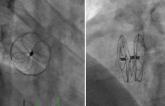

Comparison of Residual Shunt Rate and Complications: 6 Different PFO Closure Devices

October 30, 2019